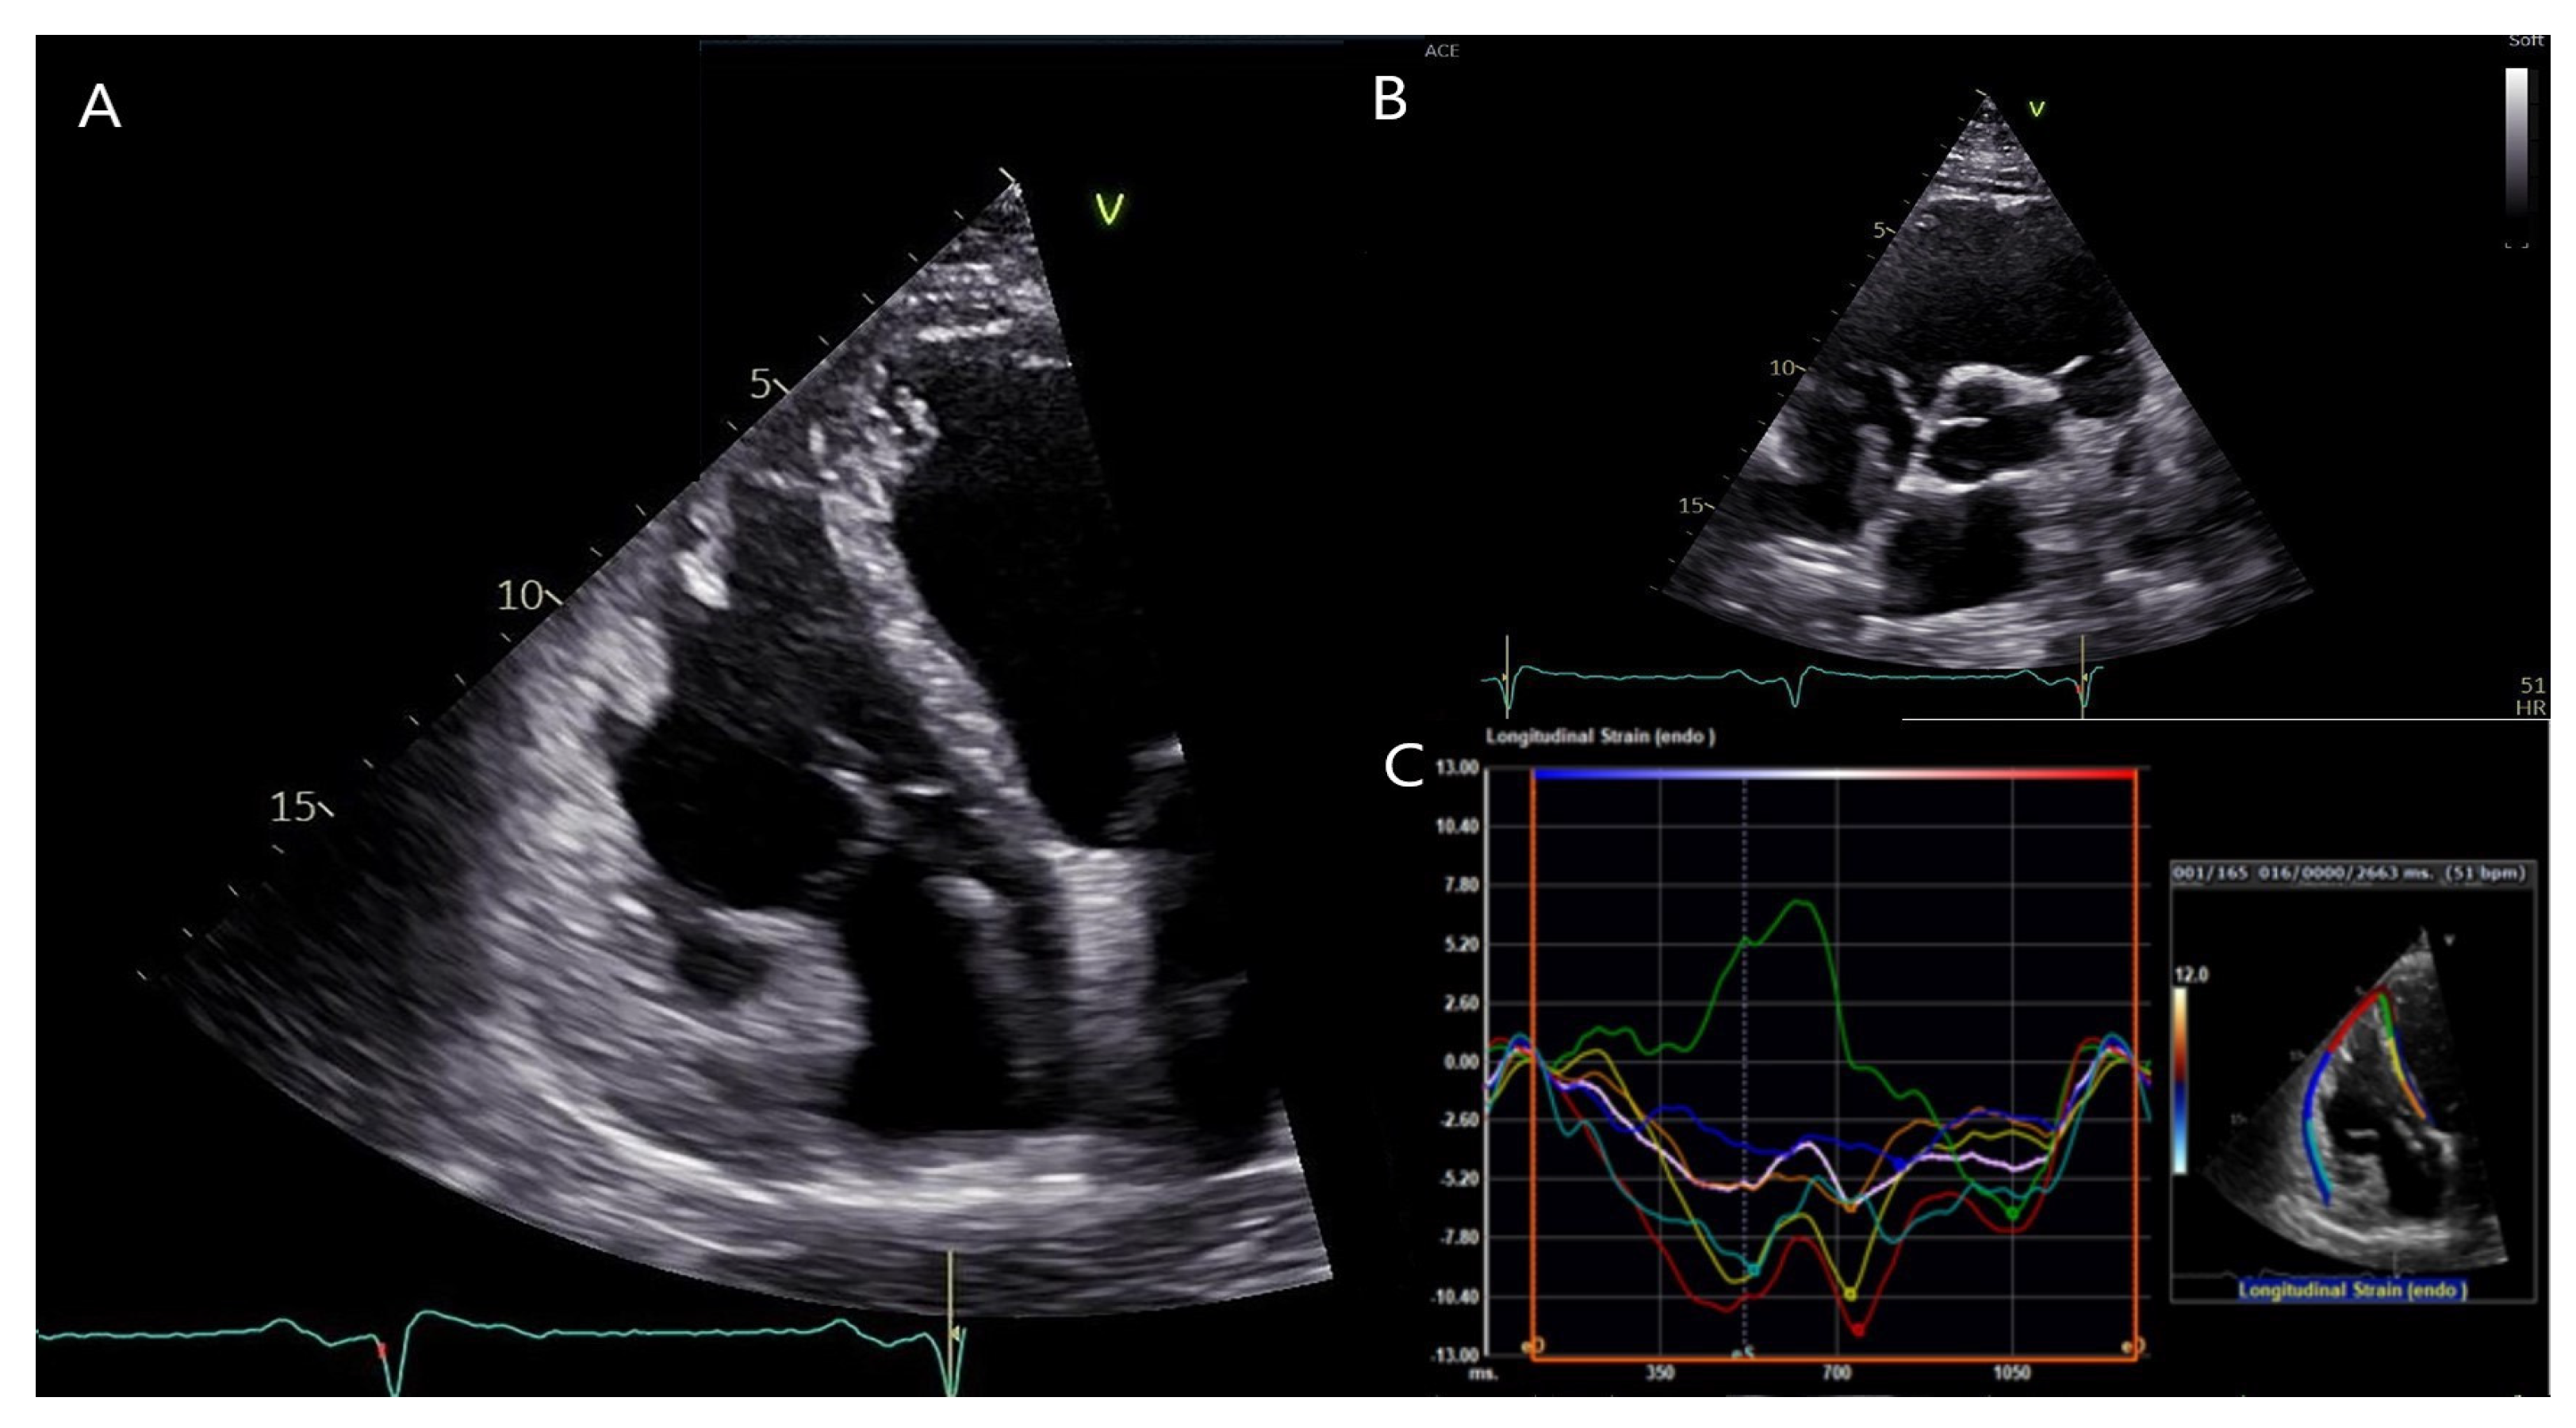

Transthoracic echocardiography of the patient showed a dilated left ventricle (LV) with moderately reduced ejection fraction (EF), akinesia of the LV inferolateral segments together with hypokinesia of the remaining segments, severe RV dysfunction with dilatation of the RV/RVOT, and akinesia of the free wall. (Figure 4 and Video S1), fulfilling both major criteria from the 2010 TFC and 2020 Padua criteria [4,5]. Both left and right ventricular global longitudinal strain were notably impaired (−11.5 and −7.0%, respectively). Similarly, the RV free wall strain was impaired (−7.7%).

Figure 4.

Transthoracic echocardiography of the patient. (A): Apical four-chamber view showing a dilated right ventricle (RV). (B): Parasternal short axis view showing RV outflow tract dilation. (C): RV free wall strain was significantly impaired (−7.7%). Segmental strain showed more impaired values for the septal, inferior and apical segments in both left ventricular and right ventricular segments, and mostly showing post-systolic shortening phenomenon. Usually, the septum is spared by the disease process in classical right dominant ARVC. Conversely, as illustrated by the green segmental strain curve, the RV apicoseptal region was dyskinetic in our patient with DSP cardiomyopathy.